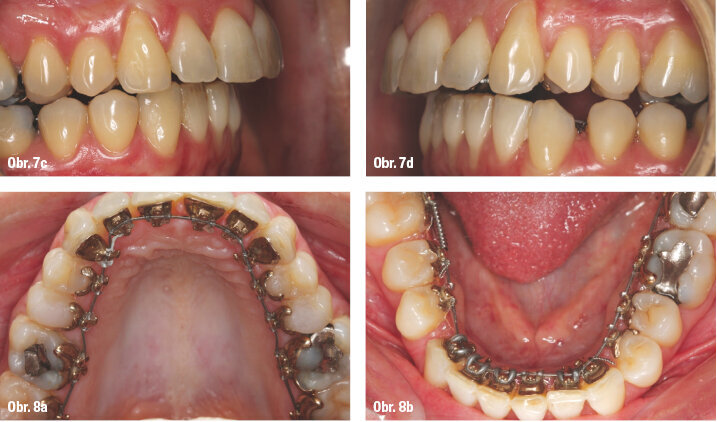

Vzhledem k tomu, že jsme plánovali uzavření mezer v dolním zubním oblouku, řetízek v dolní čelisti jsme použili až v kombinaci s ocelovým obloukem. Došlo k postupnému zhoršování jednostranné II. třídy a progresi deviace střední čáry dolního zubního oblouku (obr. 6a–c, obr. 7a–d a obr. 8a, b).

Pacientka chtěla být operována co nejdříve z kosmetických důvodů kvůli zhoršující se distookluzi dolní čelisti. K té docházelo, protože mandibula setrvávala v centrickém vztahu, a proto byl naplánován časný chirurgický zákrok. Předoperační fotodokumentaci můžete vidět na obrázcích 9a–j a 10a–g.